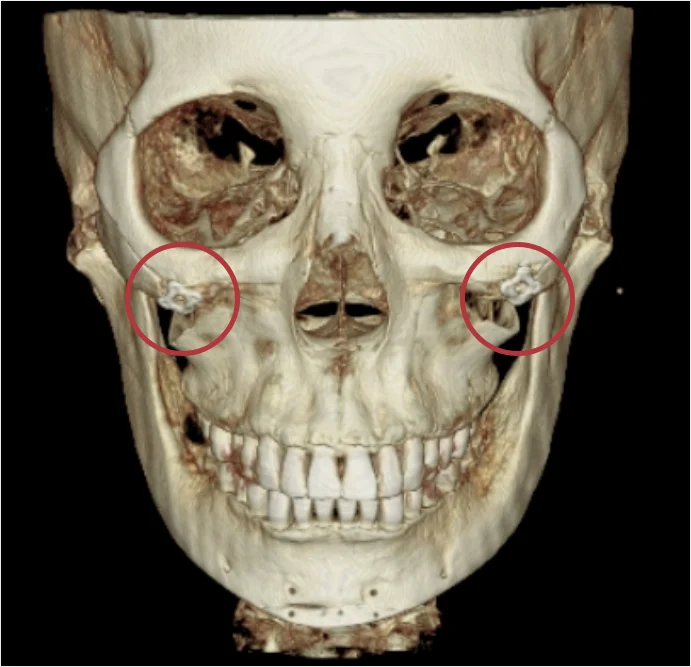

可以清楚確認嵌入在下顎與顴骨部位的金屬固定釘。

透過 CT 掃描精確確認金屬固定釘位置